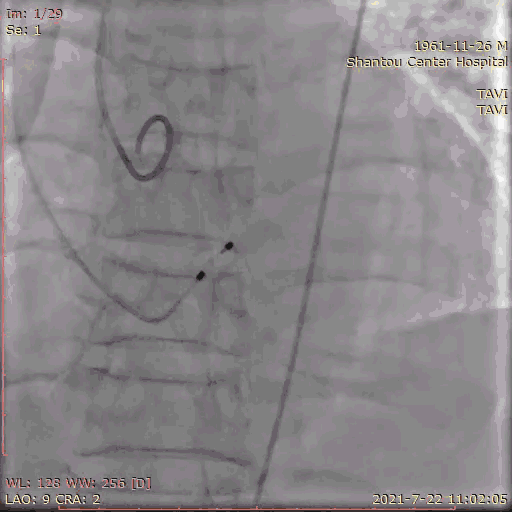

手术流程

术前怀疑冠脉有狭窄,一站式冠脉造影检查,狭窄程度无需行PCI。

冠脉造影

左右冠通畅,存在一定反流,有一定耐受能力,球扩时,循环崩溃风险较小。双侧瓣叶活动度高。

主动脉根部造影

180bpm起搏后打球囊,造影,撤球囊,停起搏;25球囊预扩后有略微漏,冠脉通畅,选择32瓣膜。

球囊预扩张